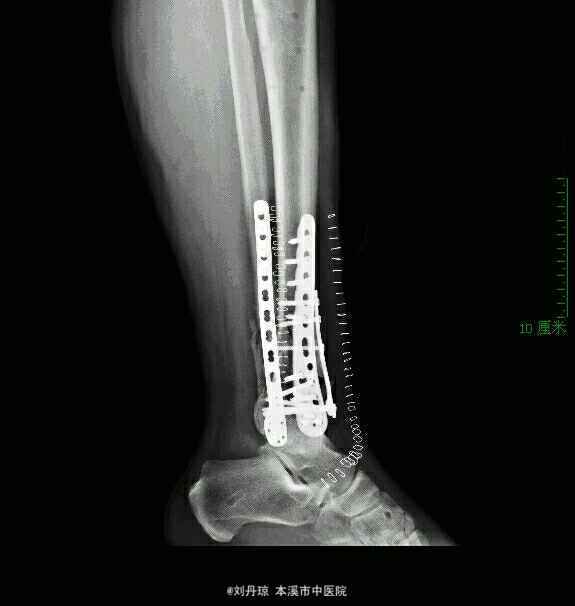

左踝pilon骨折 外固定架复位后取腓骨后缘切口,行腓骨解剖板内固定。取踝关节前内侧入路,在前内侧和前方放置接骨板。

随访2年,手术时机的选择有争议,有人建议维持距骨中立位,7~12天内手术;有人建议急诊手术或12天以后手术,还有人建议急诊行腓骨固定,择期行胫骨固定。本人建议根据软组织情况、骨折严重程度、伤后时间采取不同对策。